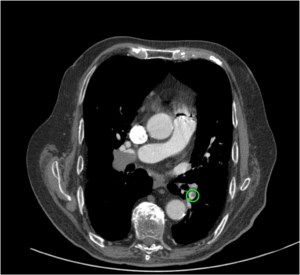

Obstrucción por trombo de la arteria pulmonar principal derecha.

Signo del Cono o Cucurucho en un corte perpendicular del vaso, sugestivo de TEP agudo.

Signo de Rail de tren en un corte perpendicular a la arteria segmentaria del LM, sugestivo de TEP agudo.